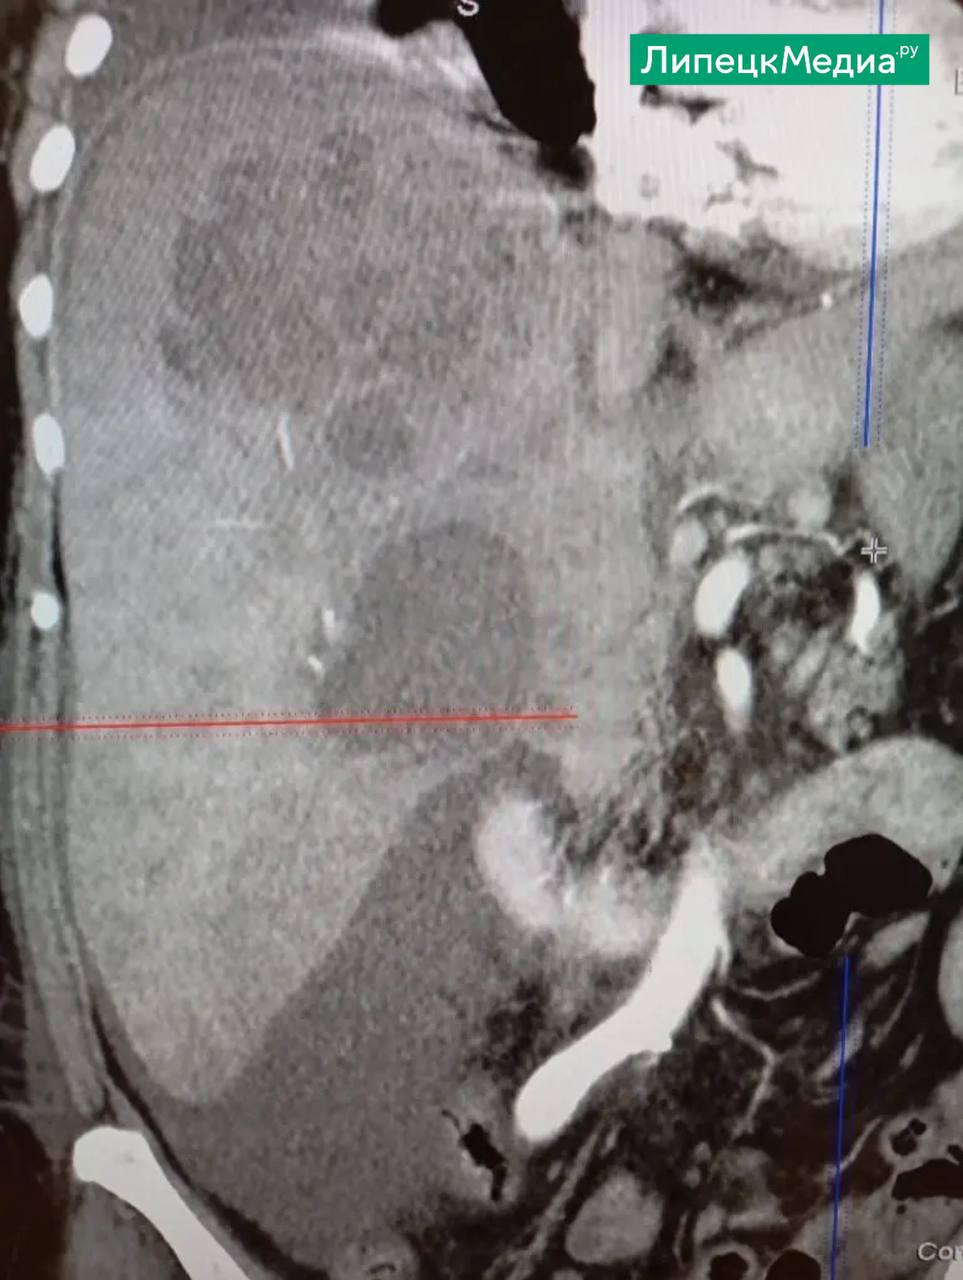

Диагноз был поставлен позже и звучал угрожающе – киста печени, осложненная нагноением.

На этой неделе врачи городской больницы «Липецк – Мед» сделали пункционное удаление гноя. Объем составил 500 миллилитров.